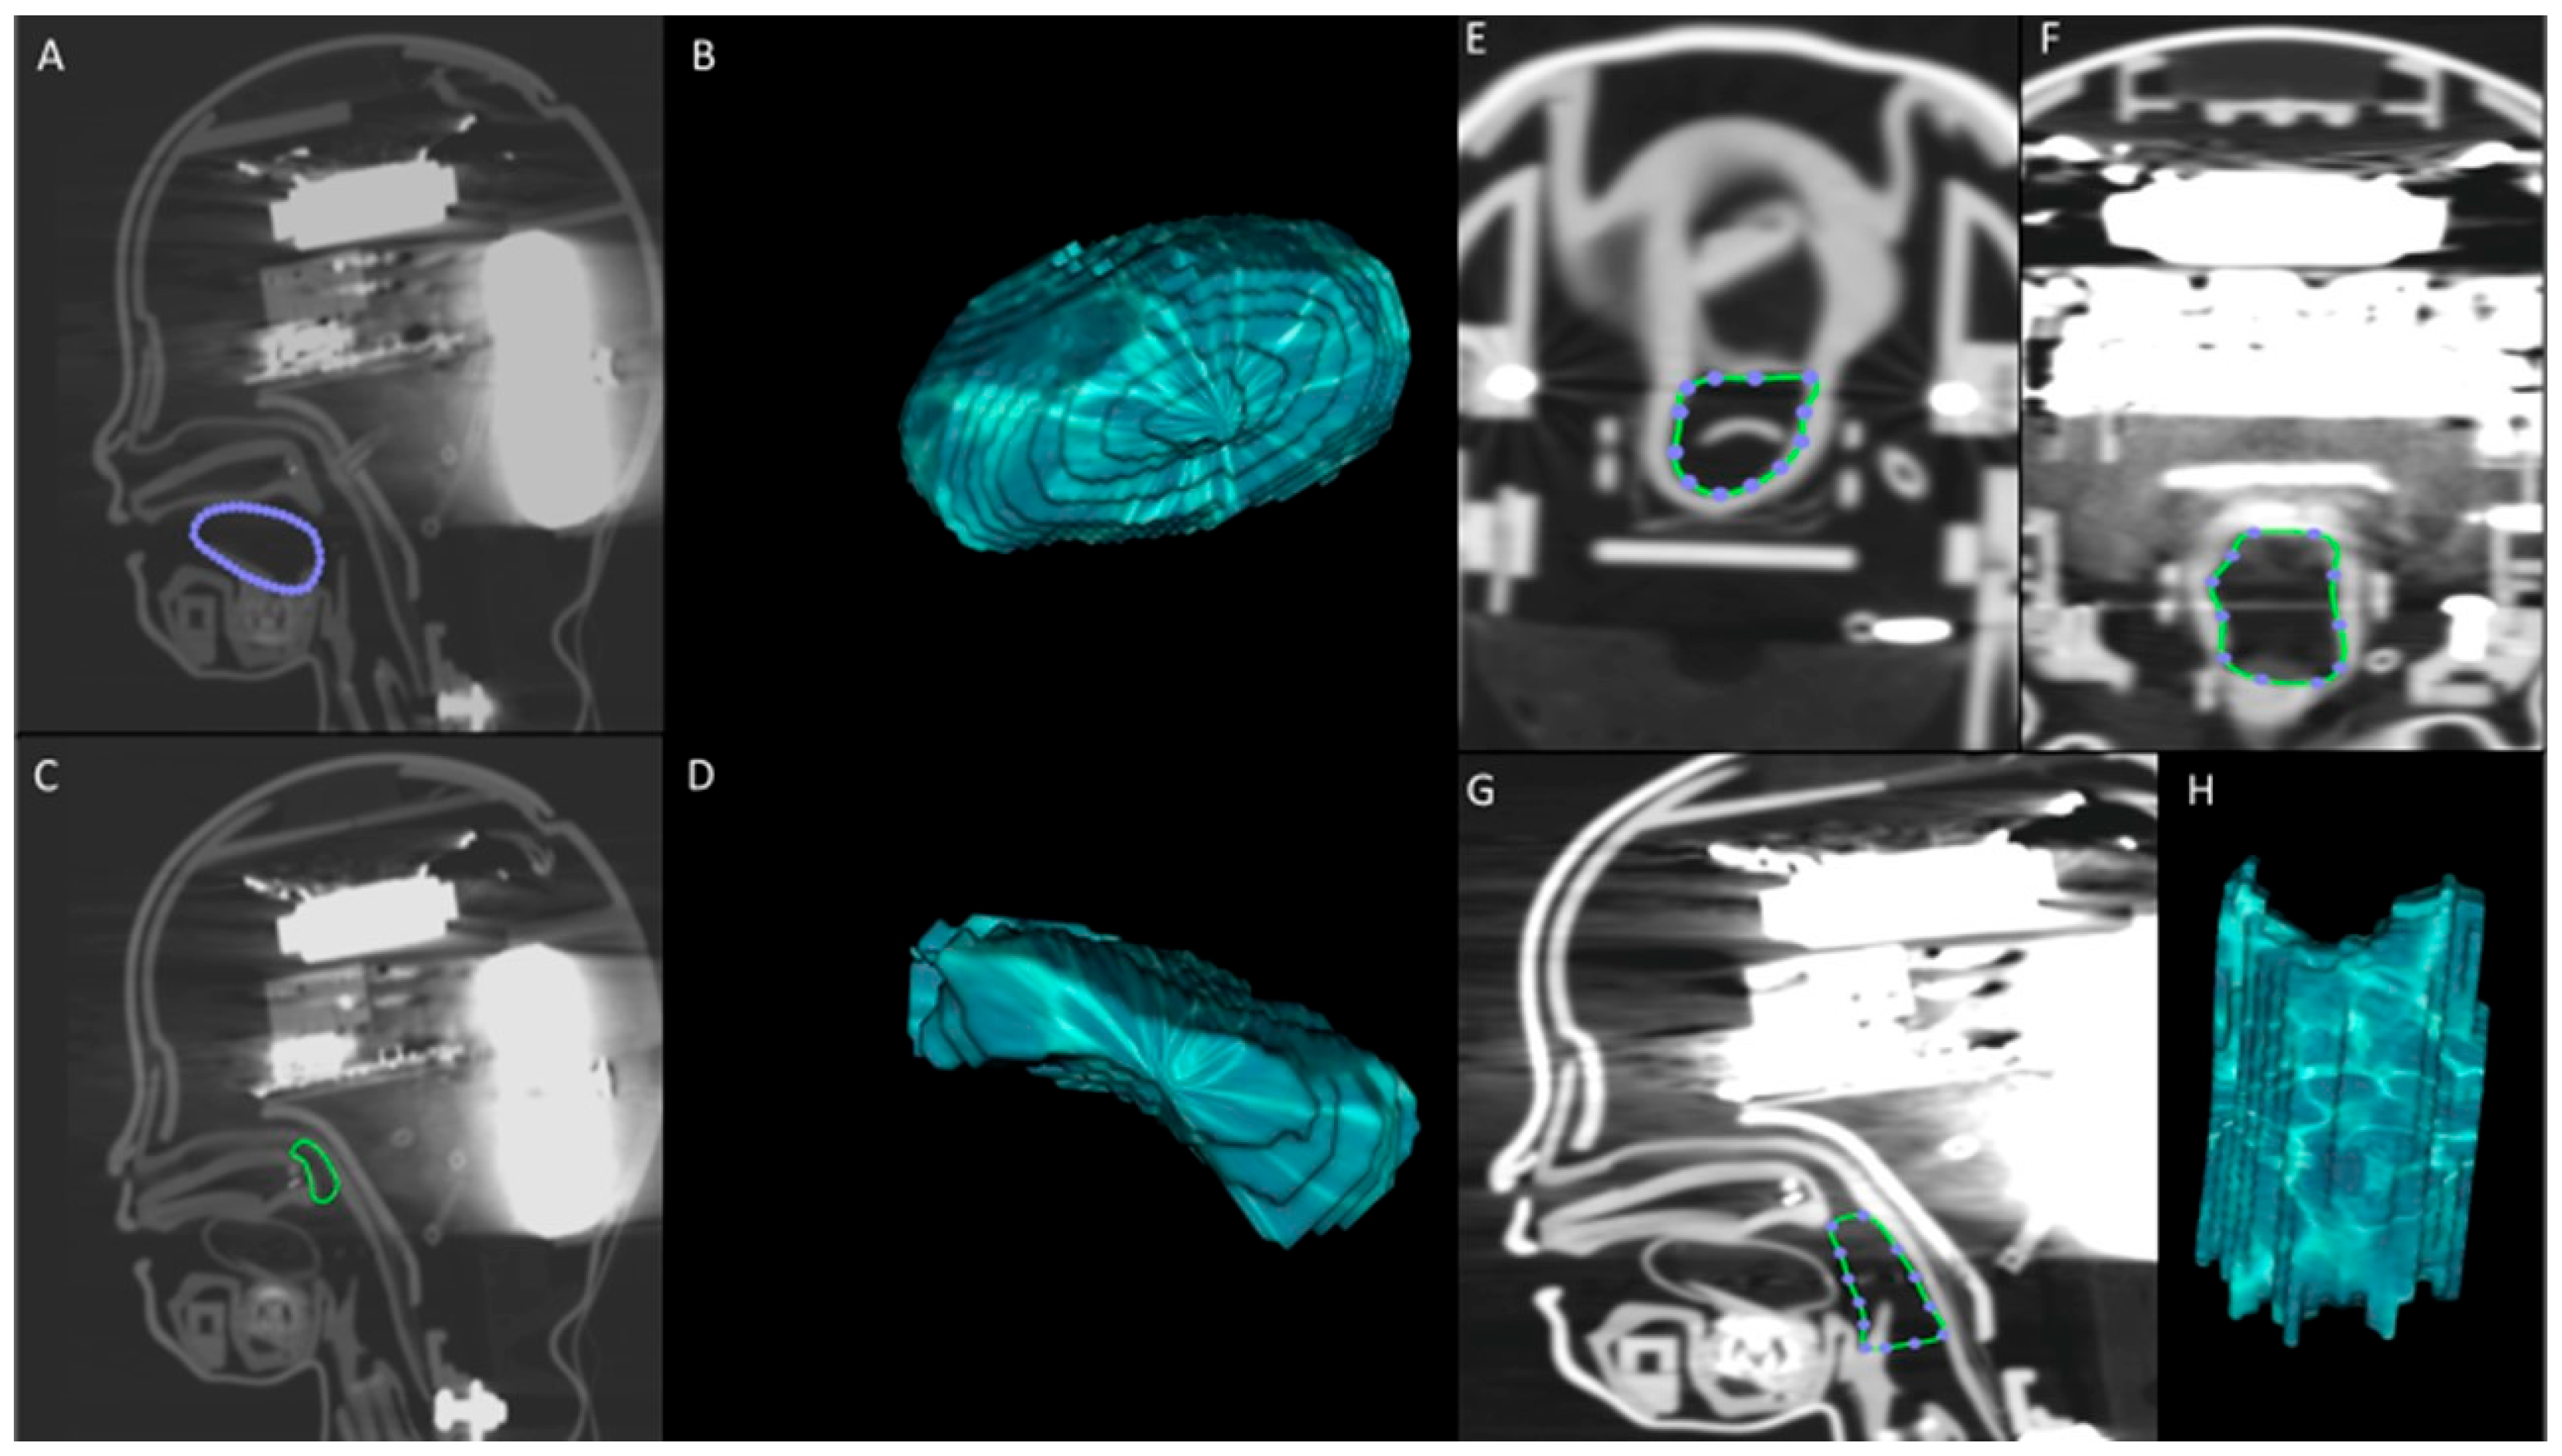

- Premature Anne (female baby born at 25 weeks—low fidelity);

- Infant Airway Management Trainer (three-month-old infant—low fidelity);

- SimBaby (9-month-old pediatric patient—high fidelity).